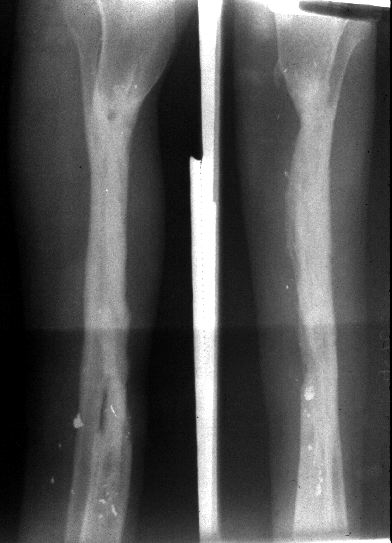

5 month Follow-Up

The patient is partial weight-bearing without pain. The soft tissue envelope is secure. The abundant soft tissue shadow indicates a transport of the soft tissues surrounding the fibular segment as well as the bone. Joint motion above and below the fracture is preserved.